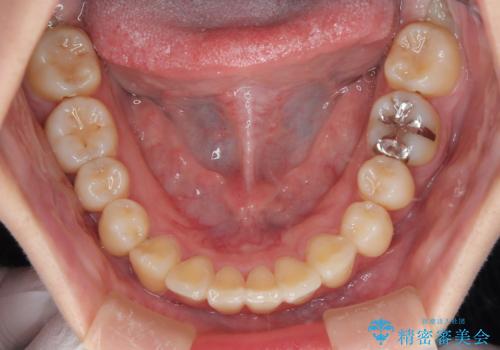

- 上下の前歯に捻れ(捻転)とガタつき(叢生)が見られます。

上の2番目の前歯の捻れに関しては、元々歯の大きさが小さい歯であるため、マウスピースにて力がかかりにくく、捻転の改善が一般的に難しくなりがちです。

下の犬歯に関しても捻れと傾き、ガタつきが大きく、歯根の長さも相まって移動の難易度が高くなりがちです。